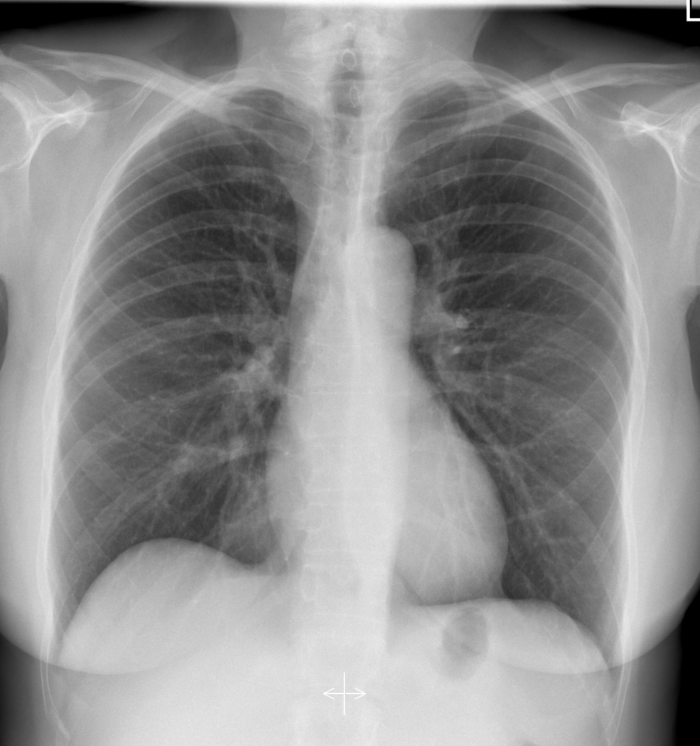

CXR for the case found here:

(CXR source: https://radiopaedia.org/cases/normal-chest-radiograph-female-1)